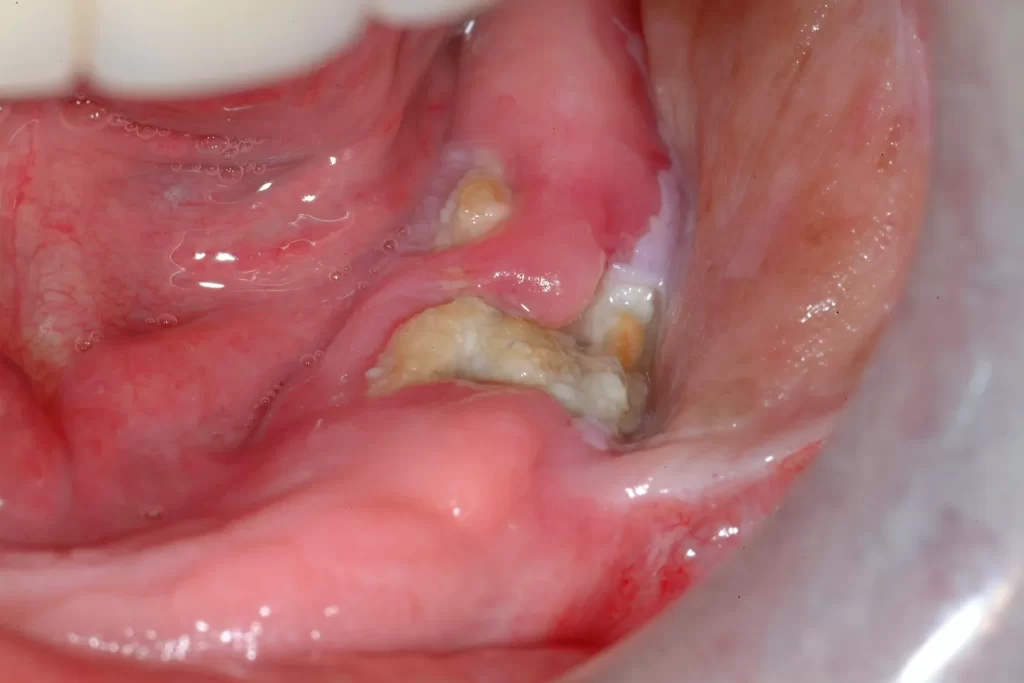

3. Lợi mưng mủ, sưng nhức

Một trong những dấu hiệu điển hình để nhận biết bạn có bị nhiễm trùng không đó là lợi mưng mủ. Bằng mắt thường chúng ta có thể nhìn thấy phần lợi chuyển sang màu đỏ đậm, sưng thậm chí mưng mủ.

Nếu vết mủ không được xử lý bị vỡ ra cũng tạo điều kiện cho vi khuẩn lan ra tấn công những vùng khác trên khoang miệng.